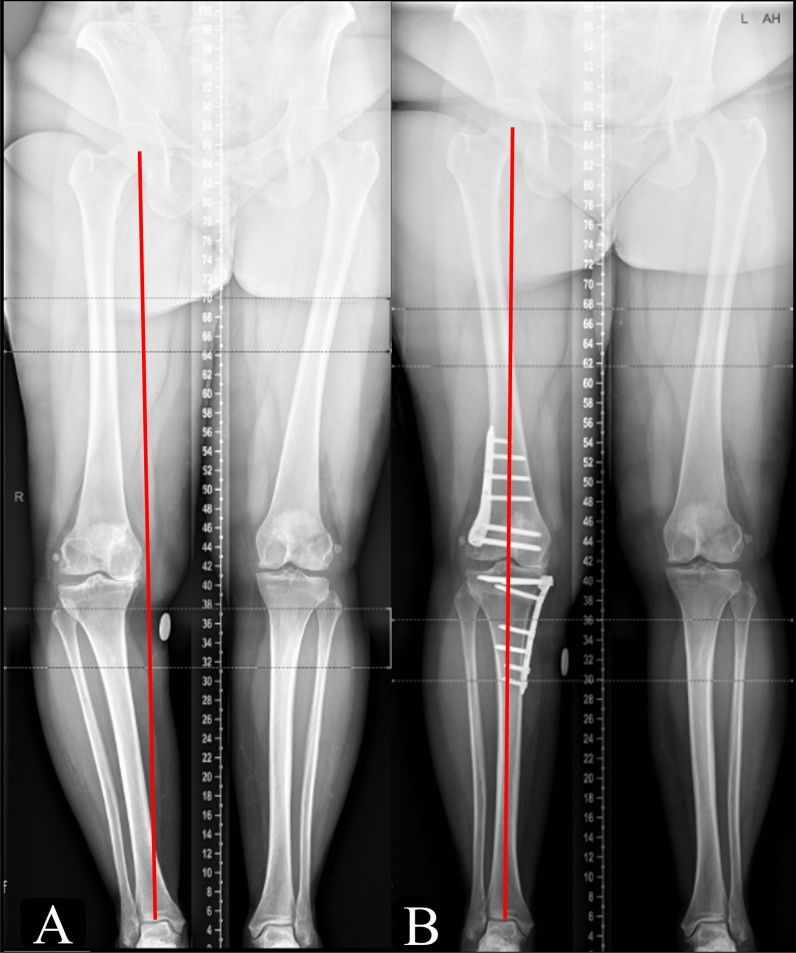

Results: A total of 58 valgization DLO cases were followed up to a mean of 10.8 ± 3 years. This comprised 74.1% males and 25.9% females, with a mean age of 47.9 ± 9.8 years and a mean body mass index (BMI) of 31.5 ± 6.3 kg/m2. The mean planned correction angles for HTO and DFO were 7.7° ± 2.7° and 7.7° ± 3°, respectively. Postoperatively, the mean mechanical tibiofemoral angle improved from -12.7° ± 3.9° (varus) to -0.4° ± 3.4° (i.e., centered around mechanical neutral), the mean medial proximal tibial angle improved from preoperative 84.3 ± 3.2° to postoperative 90° ± 2.5°, the mean mechanical lateral distal femoral angle improved from preoperative 91.6° ± 3.4° to postoperative 86.7° ± 2.5°, and the mean Mikulicz point improved from -5 ± 13.4% to 47.7 ± 14.7% (all p-values < 0.001). All PROMs significantly improved at 24 months follow-up (all p values < 0.001). The rate of osteotomy revision was 3.4%. The overall rate of total knee arthroplasty conversion was 5.2% at an average of 5.9 ± 3.1 years postoperatively. The complication rate was 8.6%. The 8- and 10-year survivorship was 97.1%, and 94.4%, respectively.

Conclusions: In this single-center series evaluating patients with varus knees and bifocal deformities, valgization double-level knee osteotomy (DLO) demonstrated favorable clinical outcomes, accompanied by a low complication rate of 8.6% and a 10-year survivorship of 94.4%. Radiographic findings from available imaging data were positive, although long-term imaging was not consistently obtained. Level of evidence IV retrospective cohort study.